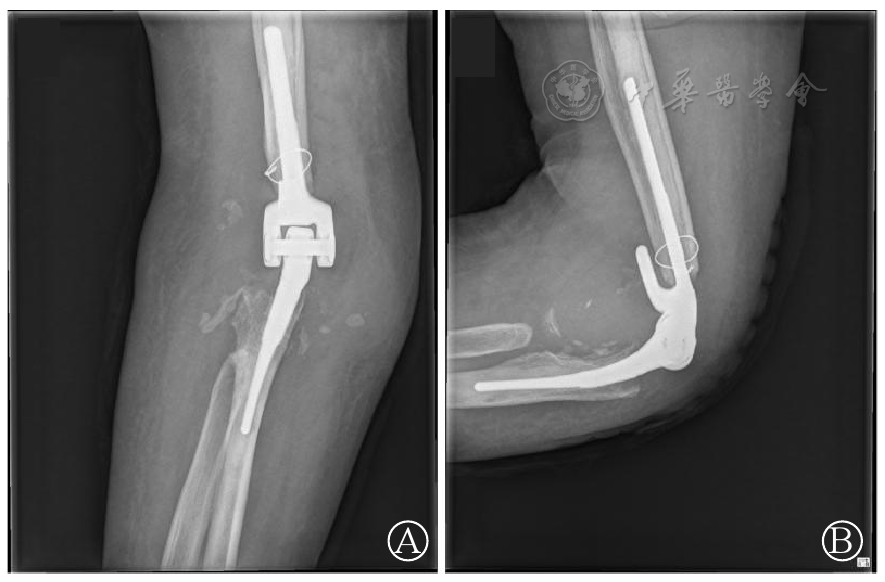

图1 右肘关节正(图A)、侧(图B)位片:右肱骨下端及尺桡骨上端见骨质吸收,关节面完全消失,可见大小不等游离碎片骨,周围软组织肿胀